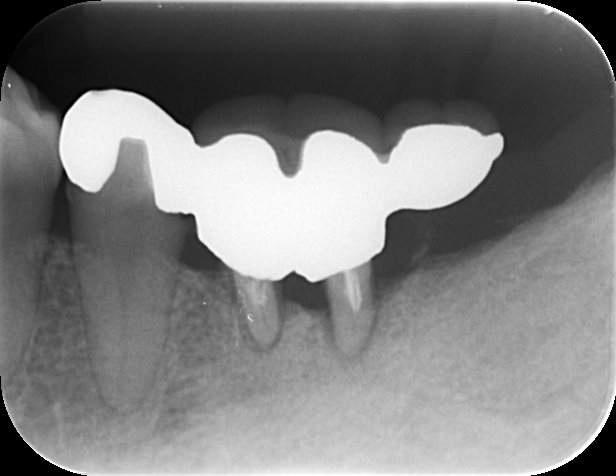

レントゲン写真

- 透過像

症例写真-1

- Befor

- After

症例写真-2

- 途中経過

| 年齢 | 50代・男性 |

|---|---|

| 主訴 | 右下歯が疼く |

| 治療内容 | ・右下6番インプラント ※1:FGG(遊離歯肉移植術)とは、足りない歯ぐきを上顎から上皮を切り取り移植する外科手術 |

| 治療費 | 合計:902,000円(税込) ■内訳 |

| 治療期間 | 9ヵ月 |

| 治療方針 | 右下の当該歯は歯根破折により保存不可能と診断しました。歯周疾患も伴っていたため抜歯後に骨吸収※1が大きく起こることが予測できました。チタンメッシュ併用骨再生誘導法(GBR※2)を選択しインプラント埋入と同時に行い自然な歯槽骨のラインを再現しました。またGBRを行う際にインプラント辺縁の付着歯肉の減少が起こる為、遊離歯肉移植術(FGG※3)を行い清掃性を考慮した形態に仕上げました。 ■治療方針の解説 治療した右下の歯をレントゲンで撮影したところ根本の部分に黒く写る箇所があり「根尖性慢性周囲炎※1」と診断。また歯周病も進行していました。 ※1 骨吸収・・・歯槽骨という歯を支える骨がなくなっていくこと |

| 担当者所見 | 主訴の右下だけでなく歯茎の腫れ、発赤があり不良補綴や不良充填など他にも治療箇所が多数ありました。プラークコントロールが不良であった為まずはブラッシング指導を行いセルフケアの重要性を理解していただくところからスタートしました。 右下6番の歯はインプラント治療を行なった結果審美的にも機能的にも患者様の満足を得ることができました。骨造成と歯肉移植も行なった為インプラントを支える十分な歯周組織の獲得ができたと思っております。 |